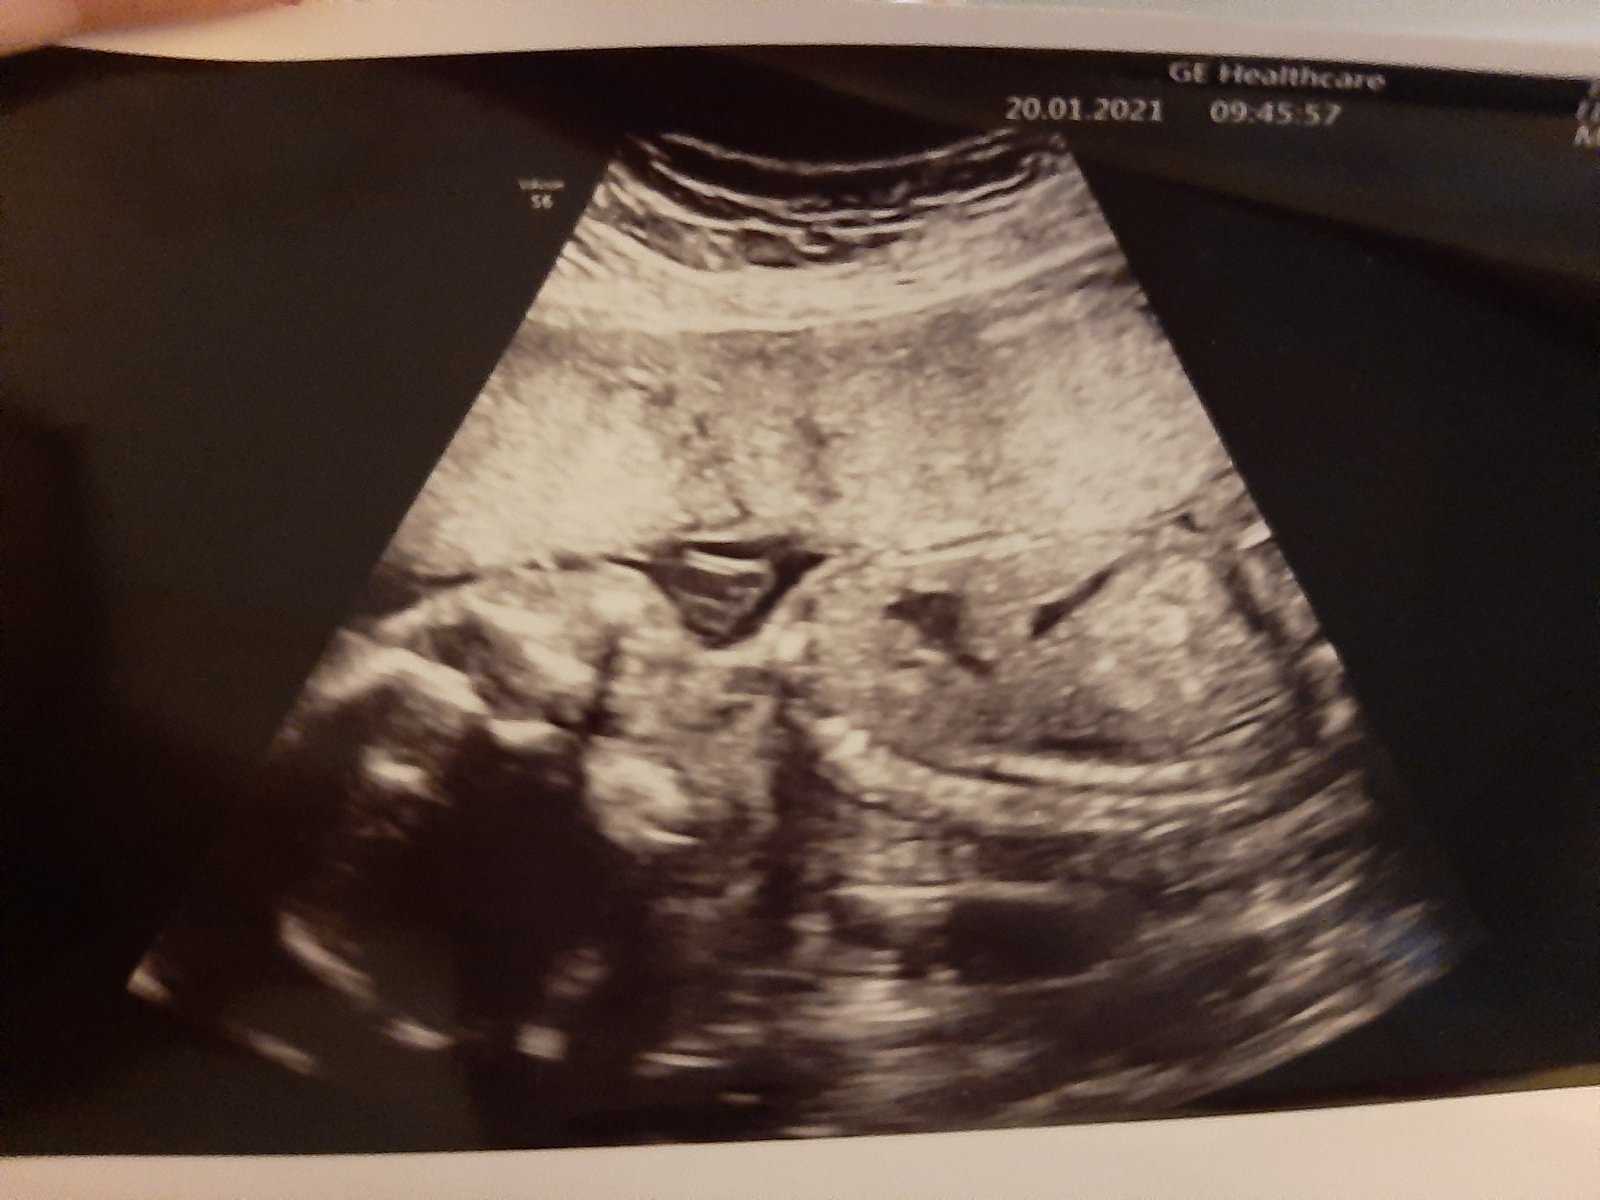

Ultrazvuková snímka v 20. týždni - tvár

Tvar je pritlačena do steny vaku a maternice, čo by tam malo byť😁